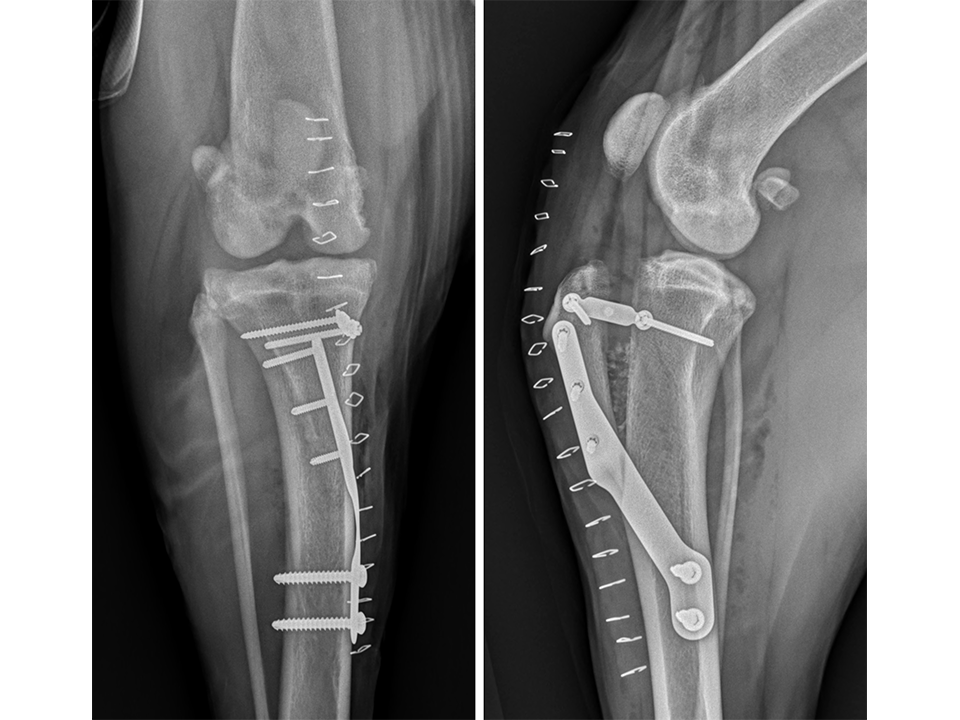

Immediate postoperative radiographs (Fig 11) revealed satisfactory implant and osteotomy positioning with the patella appropriately positioned within the femoral sulcus. There was no laxity in CrTT and the patella could not be luxated. Radiographs obtained 10 weeks postoperatively (Fig 12) revealed no evidence of implant-associated complications and smooth osseous proliferation bridging the osteotomy gap. Osteoarthritic changes within the joint were mildly progressive. Clinically at this stage, no pelvic limb lameness was evident. The range of motion of the right stifle joint was within normal limits. The stifle was stable in CrTT and the patella could not be luxated. No pain response was noted with the physical examination.